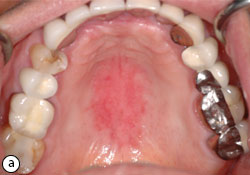

Prise En Charge De Patients Atteints De Candidose Buccale Jcda

L apparition d une plaque rouge sur le voile du palais est l un des premiers signes cliniques du cancer du palais. J ai un tâche rouge au palais depuis 2 semaine si vous savez merci de m aider car mon médecin ne ces pas de plus j ai de la fièvre et des touts petit bouton blanc à l intérieur des joues. Ces petites bosses sont généralement le résultats de grandes fièvres de problèmes d estomac ou d infections de la bouche mais peuvent également se produire après une intervention dentaire.

Les points rouges sur le palais peuvent avoir un grand nombre de causes. Nous n abordons ici que les plaques en petit nombre cliquez ici en cas de démangeaisons de la peau ou de plaques qui grattent avec des boutons sur la peau. Le palais irrité génère généralement des sensations particulièrement désagréables puisqu il s agit généralement d une inflammation palais.

Si elle n est pas traitée la tumeur va augmenter de taille toucher les structures voisines gencives joues etc et s infiltrer en profondeur en détruisant l os du palais. Lorsqu une tache rouge sur le palais est due à un aphte et que le problème est récidivant modifier certaines habitudes peut donner de bons résultats. Traiter cette affection pour réduire l inflammation est très important mais si l inflammation ne guérit pas ou qu elle se produit souvent vous devrez consulter un médecin car il pourrait s agir d une infection qui nécessite un traitement médical.